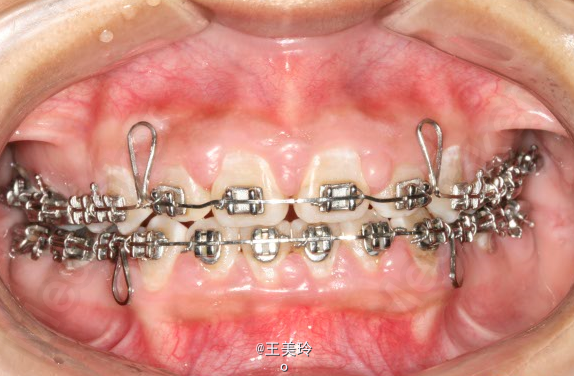

主诉:面突求矫治 既往史:无矫治史,无牙科治疗史,无外伤史,无过敏史,无口腔不良习惯,无家族遗传史 口腔检查:恒牙列,A7-B7;C7-D7。个别牙齿不齐 尖牙磨牙I类关系轻度深覆合深覆盖 下颌中线右偏约2mm 双颌前突,突面型 关节无弹响无压痛

诊断:安氏I类双颌前突 矫治计划 1.MBT矫治技术 2.拔牙矫治,拔A4B4C4D4 3.闭隙曲,J勾内收前牙 4.矫治结束后尖牙,磨牙,覆合覆盖正常 5.面型有所改善